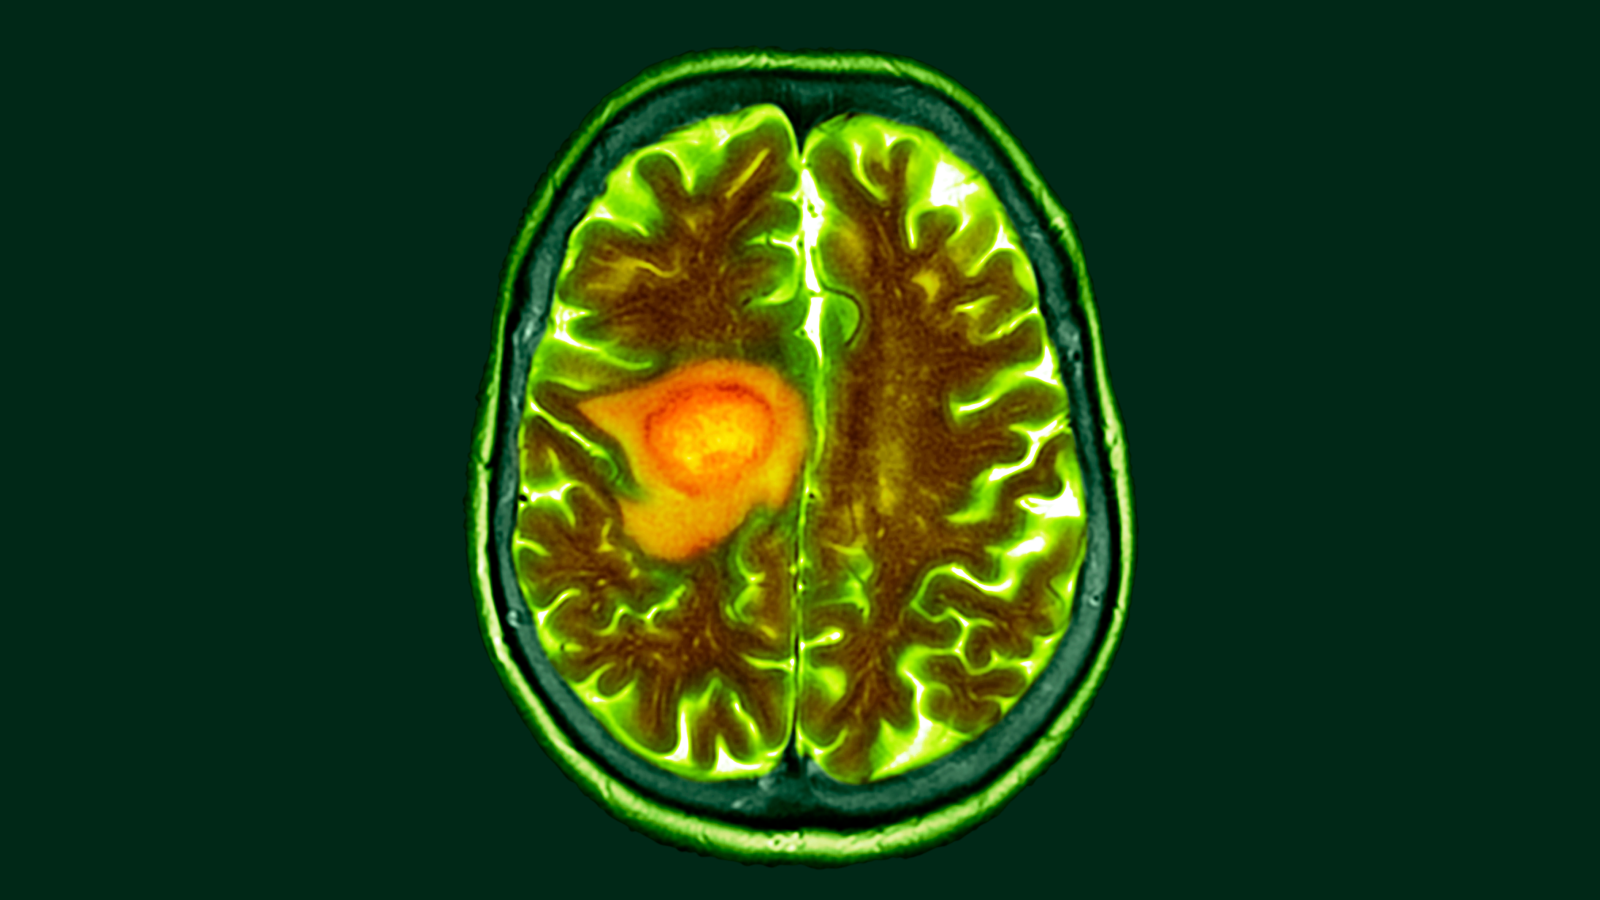

Dietary changes could make lethal brain cancer glioblastoma more vulnerable to cancer therapy, new research suggests.

The study, coordinated by Dr. Dan Waal, an oncologist at the University of Michigan, evaluated how glioblastoma distorts its metabolism in both human and animal brains. The study ambitiously combined laboratory research and clinical practice by drawing some of its data from tissues taken from the brains of patients undergoing cancer surgery. This study required collaboration with experts in brain surgery, metabolic pathways, and molecular analysis in humans and rodents.